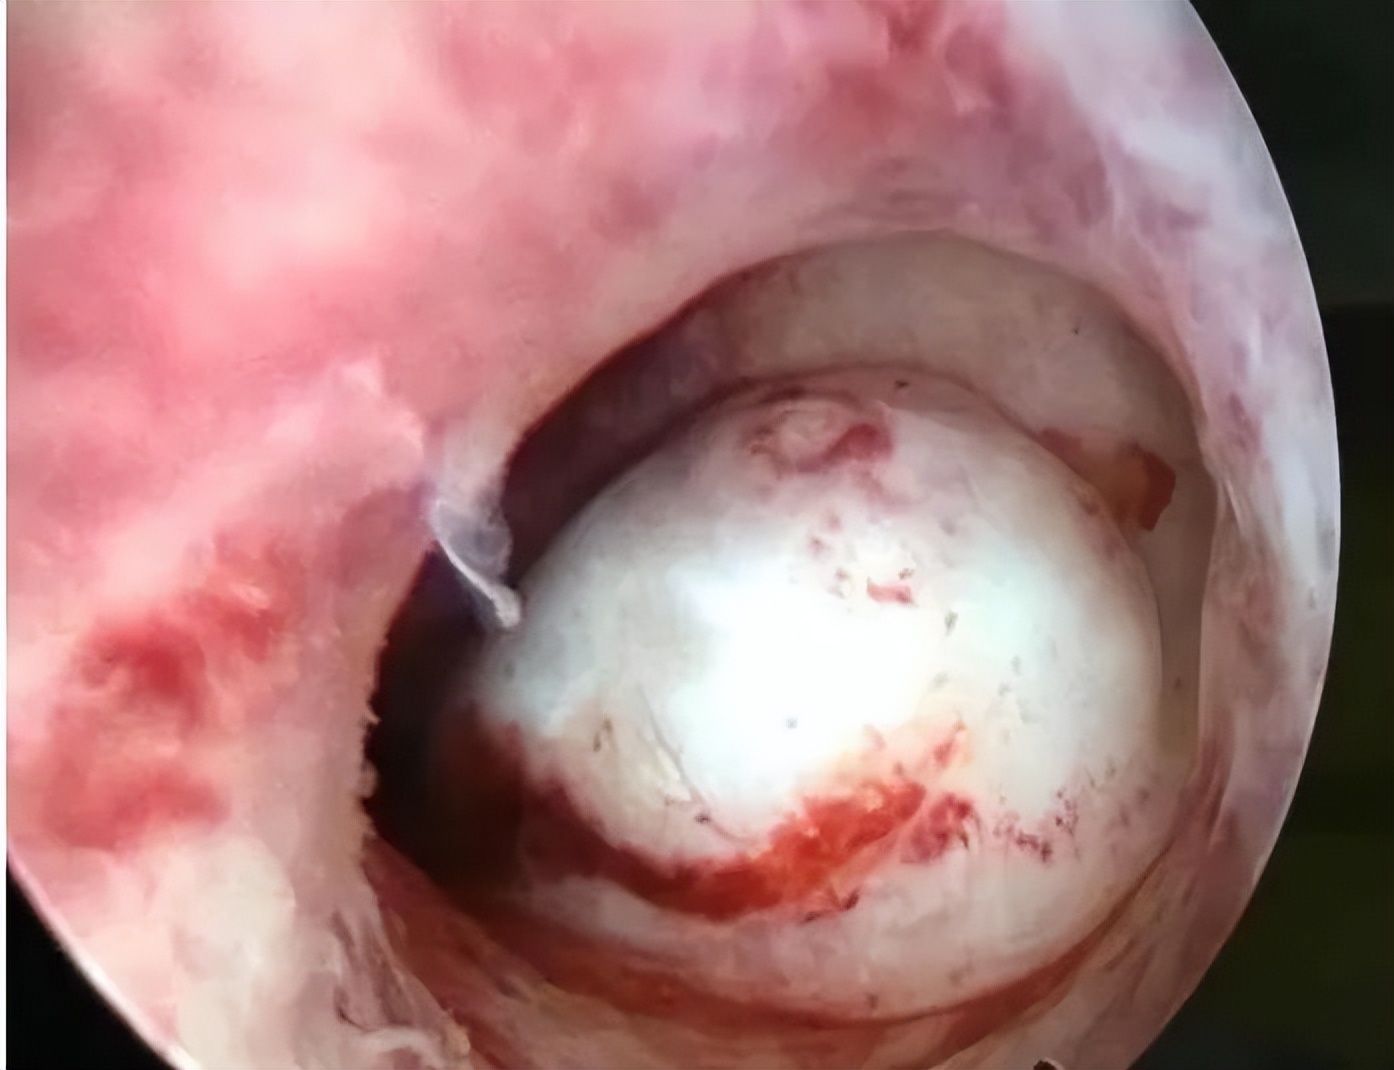

子宫黏膜下肌瘤